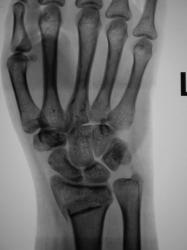

У пациентки снят ГИПС. Пациентка направлена на рентгенографию лучезапястного сустава с целью рентгенологического подтверждения консолидации.

Настораживает повышенная плотность отдельно лежащего фрагмента по передней поверхности метафиза луча на фоне  легкой общей минералопении, признаков формирования костной мозоли не видно - есть основания зподозрить нарушение его трофики с последующим формированием секвестра.

Консолидации нет.